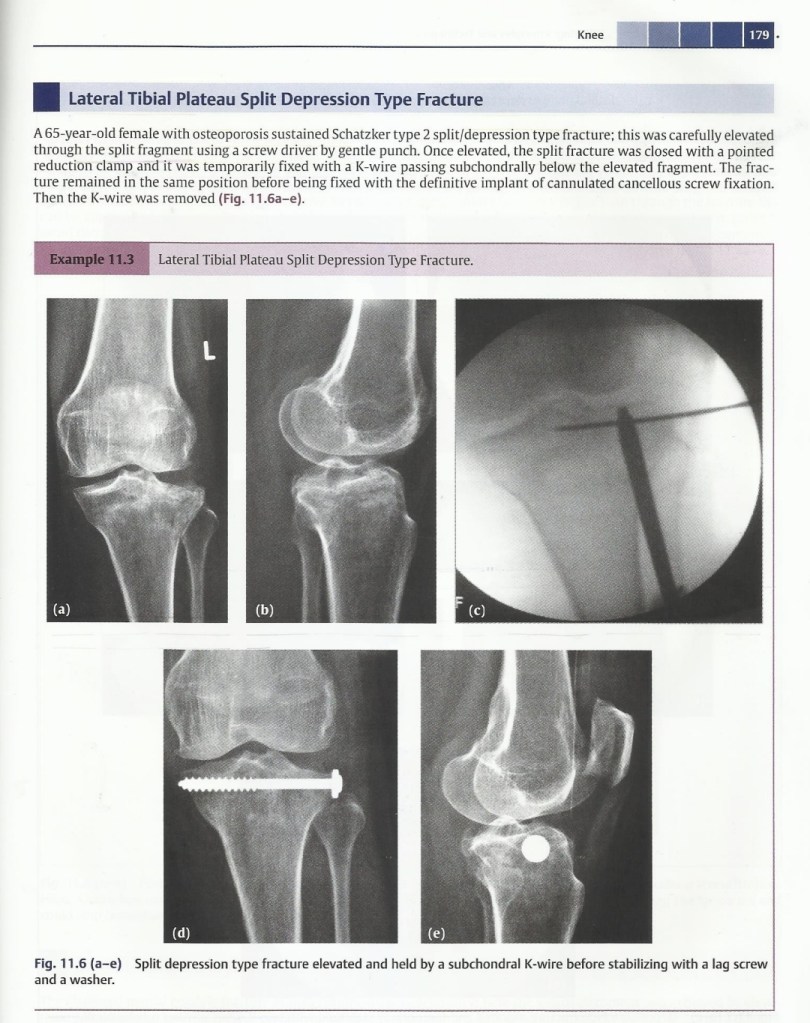

Lecture Tibial plateau fracture